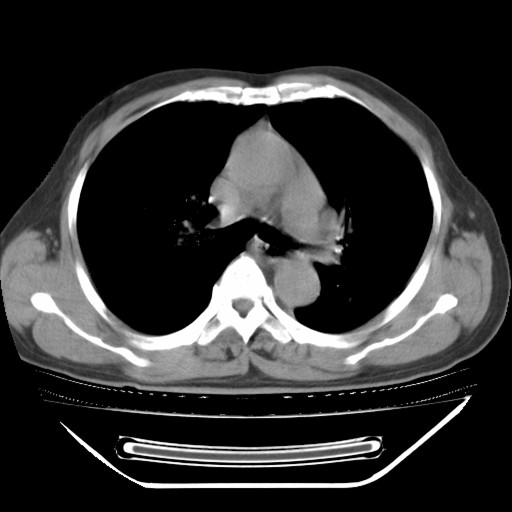

以下是引用hhcckk在2009-5-29 10:34:00的发言:[br]左下肺片絮状边缘模糊影,考虑感染,建议治疗后复查[br]